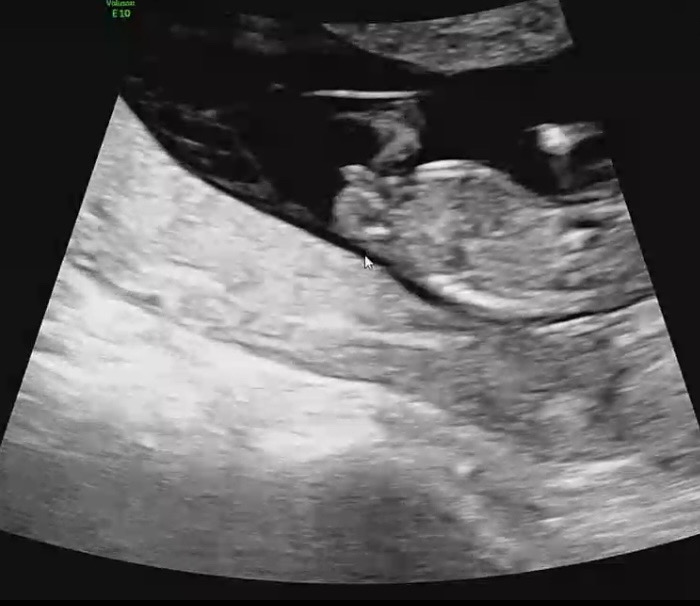

안녕하세용 11주 6일에 촬영한 초음파예용 각도법으로 아들,딸 구분가능할까용?

저눈 생식기 선 일자여서 딸 ! 장꾸맘 해보셔ㅛ어용 ??